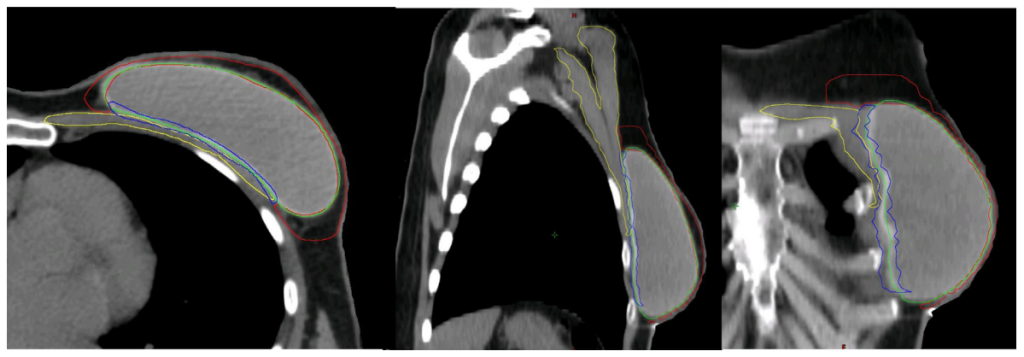

Hình 4c. CTVp_chestwall với phần trước (Đỏ) và sau (Xanh biển) trong trường hợp túi độn trước cơ ngực (Xanh lá cây). Cơ ngực (Vàng)

Sau IBR-i sử dụng túi độn trước cơ ngực, CTVp_chestwall bao gồm 2 phần phân chia bởi túi độn:

(1) Phần trước: Giữa da và túi độn, chứa đựng mạng lưới bạch huyết dưới da và mô tuyến tồn dư (Nếu có) (Hình 4C, thể tích giới hạn bởi đường viền đỏ);

(2) Phần sau: Giữa túi độn và cơ ngực/thành ngực, chứa đựng mô tuyến tồn dư (Nếu có) (Hình 4c, thể tích giới hạn bởi đường viền xanh biển); chỉ trở thành một phần của CTV trong các trường hợp có các yếu tố khối u bất lợi (Bảng 1).

Bao phủ toàn bộ trong trường hợp túi độn trước cơ ngực: Có các yếu tố bất lợi (Thể tích màu xanh biển trên hình 4c)